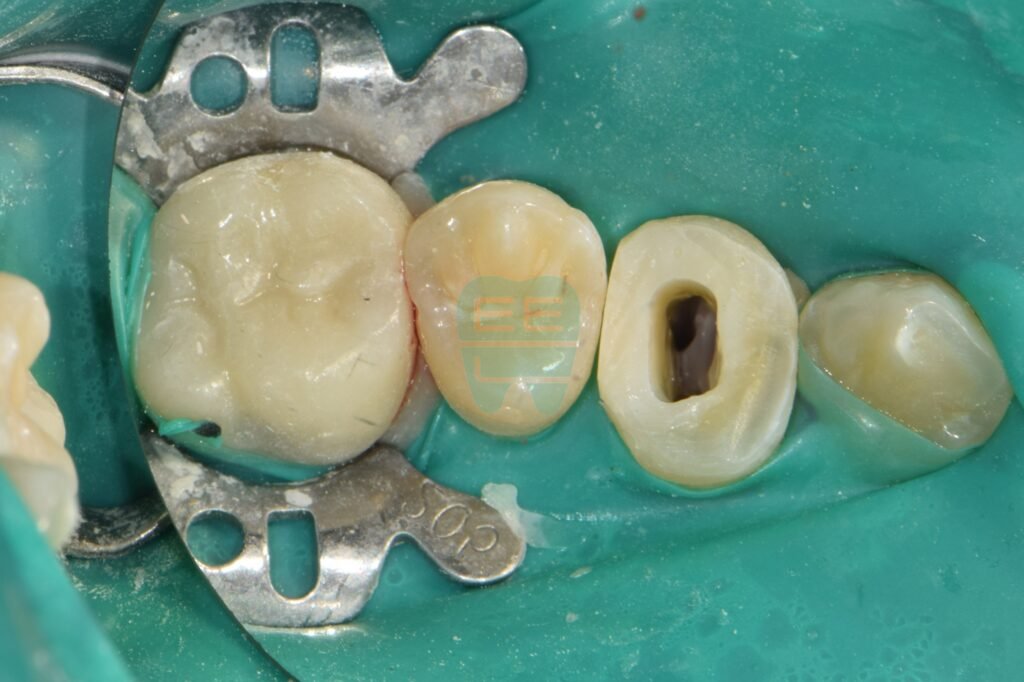

4. 신경치료 및 지르코니아 크라운 수복 (After)

레진 벽 덕분에 무균 상태에서 꼼꼼하게 신경치료를 마칠 수 있었습니다. 이후 치아를 단단하게 보강하고, 최종적으로 지르코니아 크라운을 씌워 치료를 마무리했습니다.

치료가 완료된 모습입니다. 잇몸이 차오르고 피가 나던 처음 모습은 온데간데없고, 튼튼하고 예쁜 치아로 다시 태어났습니다.